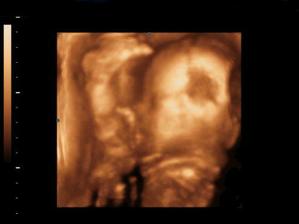

Prve foto - 3 mesiac